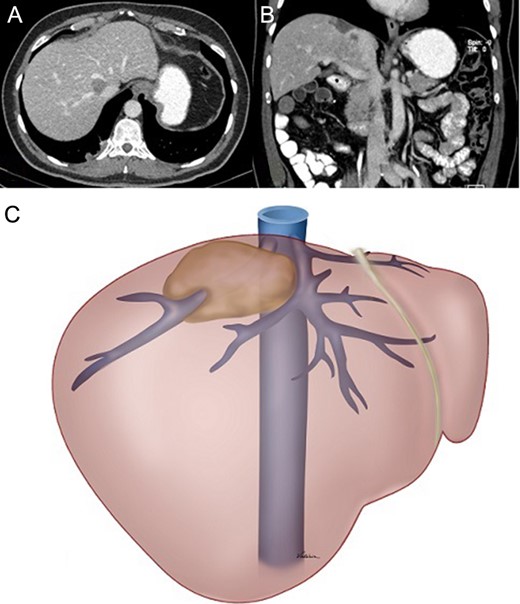

Computed tomography (CT) disclosed a 4.0 × 2.0 cm lesion in Segment 8 involving the entire circumference of the right hepatic vein (which was still partially patent), extending medially to the middle hepatic vein and posteriorly to the retrohepatic inferior vena cava (IVC) (Fig. 1).

(A) and (B) Preoperative CT showing displacement of the tumour and its relationship with the right and middle hepatic veins and the IVC. (C) Schematic drawing of the tumour.